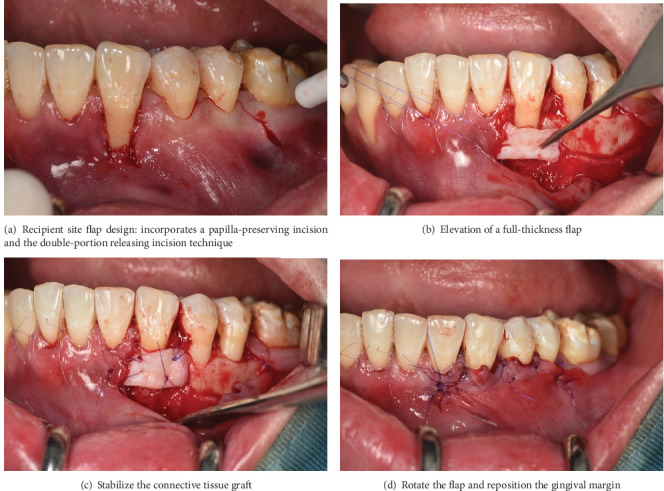

背景:目前已经提出了几种治疗牙龈萎缩的方法,并取得了积极的效果和临床可接受的结果。然而,大多数需要两阶段的手术,有一些缺点。本临床报告描述了改良的旋转皮瓣技术结合双成分释放切口和单侧隧道入路治疗牙龈退缩的治疗过程和临床结果。方法:32岁男性,非吸烟者,经正畸治疗后,33牙后退6mm, 43牙后退8mm。从硬腭取8 × 12 × 1.5 mm大小的结缔组织移植物。采用裂厚法在犬的内侧建立隧道皮瓣。在第二前磨牙的远端放置一个缩小的切口,包括一个弯曲的部分,遵循犬齿和前磨牙的颈椎轮廓,并以双部分释放切口结束。将移植物插入隧道,将牙龈瓣重新定位并固定以覆盖暴露的牙面。结果:随访6个月和1年,平均根管覆盖率100%,无疼痛和牙敏。结论:虽然需要进一步的研究和长期随访来评估该手术的有效性,但本病例报告表明,该技术不仅增加了根覆盖,而且仅在一次手术预约中就使粘膜宽度角化。

Background: Several techniques have been proposed to deal with gingival recession and gain positive effectiveness and clinically acceptable results. Nevertheless, most require a two-stage surgical procedure with several drawbacks. The present clinical report describes the treatment procedure and clinical outcomes of a modified rotated flap technique incorporating a double-component releasing incision and one-sided tunnel approach for the management of gingival recession. Methods: A 32-year-old male nonsmoker presented with a recession of 6 mm at tooth 33 and 8 mm at tooth 43 after orthodontic treatment. An 8 × 12 × 1.5-mm-size connective tissue graft was harvested from the hard palate. A tunnel flap was created on the mesial side of the canine using split-thickness technique. A reduced incision was placed distal to the second premolar, consisting of a curved segment that followed the cervical contours of the canine and premolars, and concluded with a double-portion releasing incision. The graft was inserted into the tunnel, and the gingival flap was repositioned and secured to cover the exposed tooth surface. Results: After the 6-month and 1-year follow-ups, the mean root coverage rate was 100% without pain and tooth sensitivity. Conclusions: Although additional studies and long-term follow-up will be needed to evaluate the effectiveness of this procedure, this case report showed that this technique not only increases root coverage but also keratinized the mucosa width in only one surgical appointment.